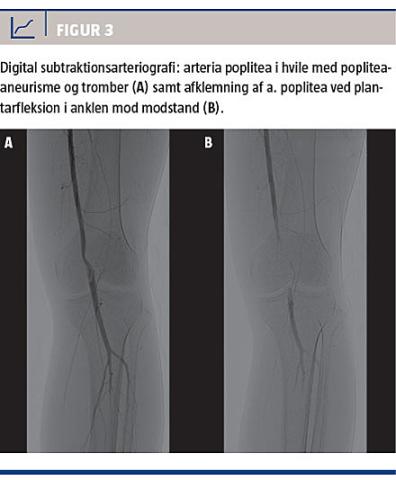

Digital subtraktionsarteriografi

Det karakteristiske arteriografiske fund ved arteria iliaca-endofibrose er en excentrisk stenose, der inddrager arteria iliaca externa. Vinkling af arterien kan ofte visualiseres ved fleksion i hofteled (Figur 2)

[1, 12, 18, 22].

Afklemning af arteria poplitea ved plantarfleksion

i ankelleddet mod modstand er diagnostisk for arteria poplitea-afklemningssyndrom (Figur 3). Herudover vil medialdeviation af arteria poplitea oftest opfattes som patognomonisk for tilstanden [2, 9, 11, 15].